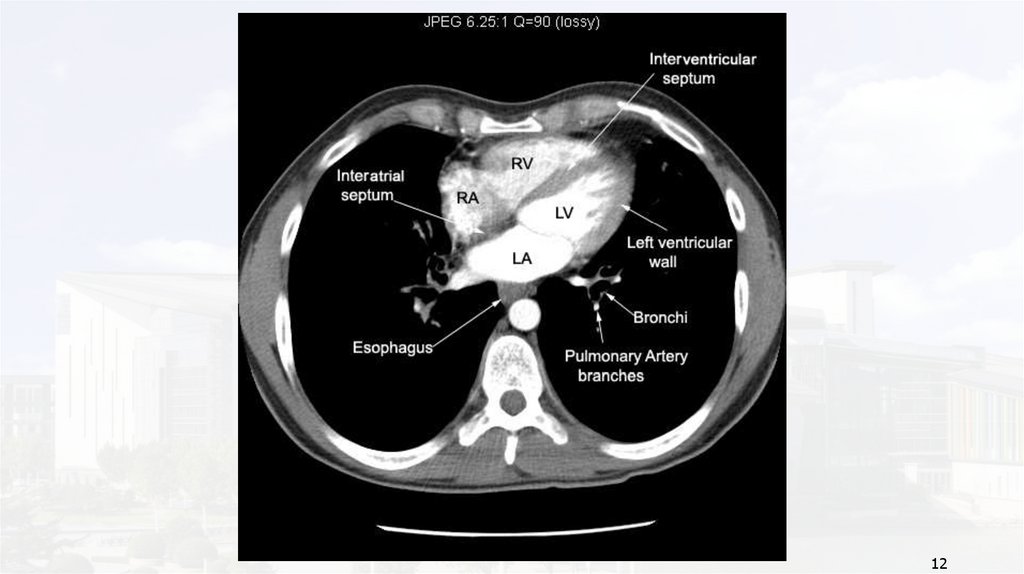

12.

12